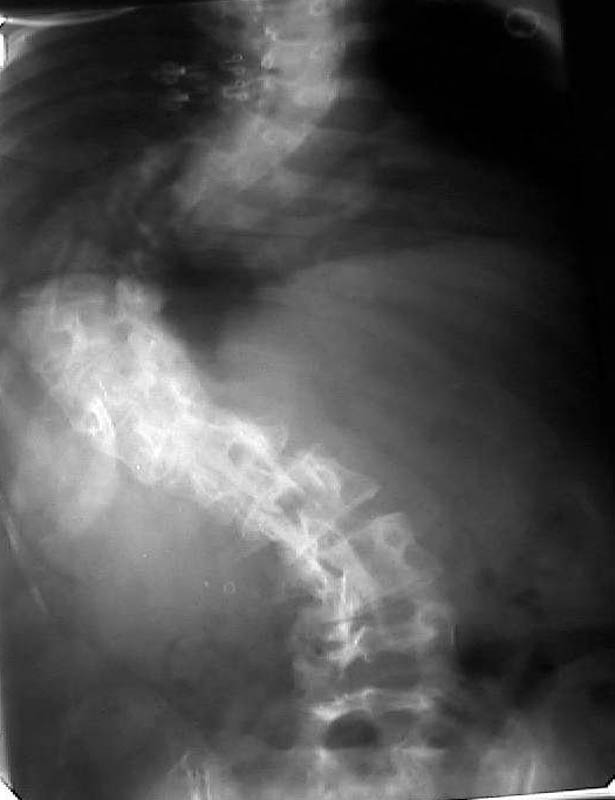

Мужчина, 38 лет. Двусторонний диспластический коксартрз, кифосколиоз.Правый сустав прооперирован 12.12.00, левый - в апреле 2003 г. Справа вывихнулась <чашка>.

Предполагается заменить <чашку>, наростив крышу <тутопластом>? Возможно ли использовать бесцементную <чашку>? Мнения? Заранее благодарю! С уважением,А.В.Владзимирский